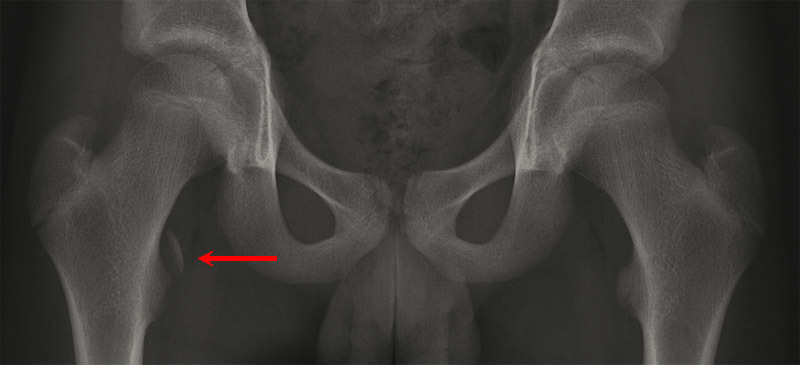

© P. Journeau, E. Polirzstok, F. Launay, D. Barbier (La Revue du Praticien)

Avulsion de l'insertion du muscle psoas. Voir : P. Journeau, E. Polirzstok, F. Launay, D. Barbier. Lésions osseuses de sollicitation excessive chez l’enfant sportif. Rev Prat 2015;65(8);1084-90.